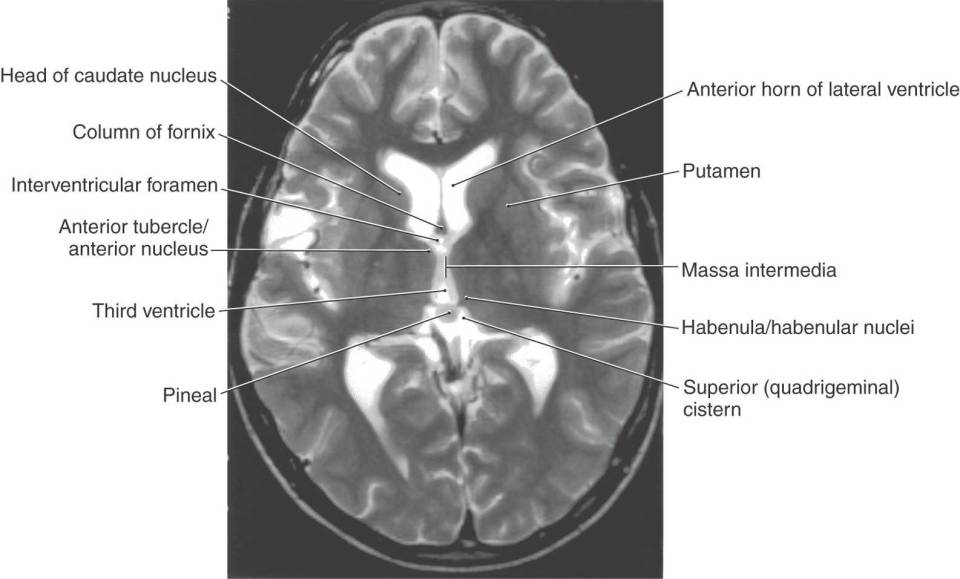

massa intermedia

thalamus and basal ganglia

normal brain anatomy axial coronal